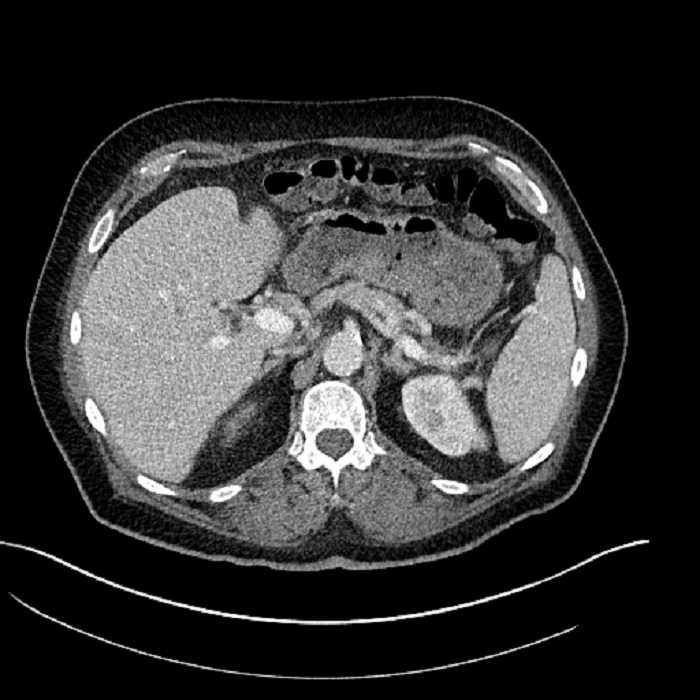

• Large fluid density structure in hepatic segments 7 and 8 measuring 10 x 7 x 7 cm with internal septation and circumferential ill-defined low density compatible with edema

• Peripherally enhancing subcapsular collections along the anterior margin of the left hepatic lobe measuring 3 x 1 cm and 2 x 1 cm

• Clearly marginated fluid density structure in segment 7 and several other scattered tiny hypodensities, which likely represent cysts

Acute sigmoid diverticulitis complicated by a small contained perforation and a large abscess in the right hepatic lobe. Additional small subcapsular abscesses along the anterior margin of the left hepatic lobe.

• The classic CT imaging appearance is a double target sign with internal low density surrounded by an internal enhancing rim (capsule) and a low density external rim (edema)

Hepatic abscess showing the double target sign with low density internally surrounded by a thin inner enhancing rim (red arrow) and ill-defined outer low density rim (yellow arrow). Blue arrow indicates an internal septation. Red arrows: additional smaller subcapsular abscesses. Red arrow: focal contained perforation associated with diverticulitis.